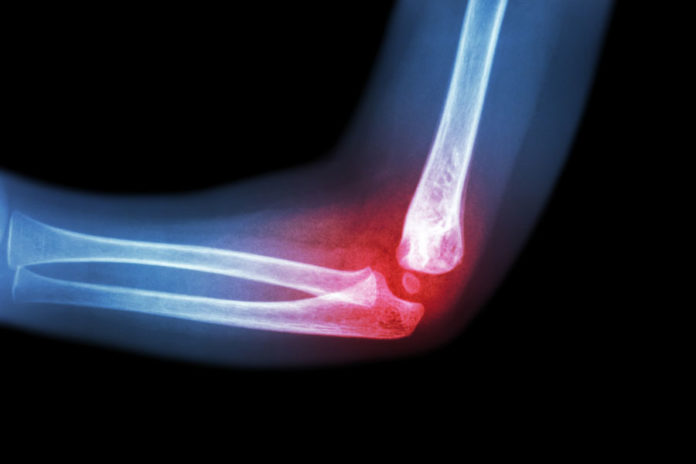

Le fratture da fragilità – in particolare quelle di femore, vertebre, polso e omero – rappresentano una delle principali complicanze dell’osteoporosi. Non solo riducono l’autonomia e la qualità di vita, ma possono avere ripercussioni importanti anche sul piano sociale e sanitario. Per questo motivo la prevenzione gioca un ruolo fondamentale.

Attraverso la diagnosi precoce, ad esempio con la MOC (Mineralometria Ossea Computerizzata), è possibile valutare la densità minerale delle ossa e intervenire tempestivamente con trattamenti mirati, sia farmacologici che non farmacologici, in grado di ridurre significativamente il rischio di fratture.